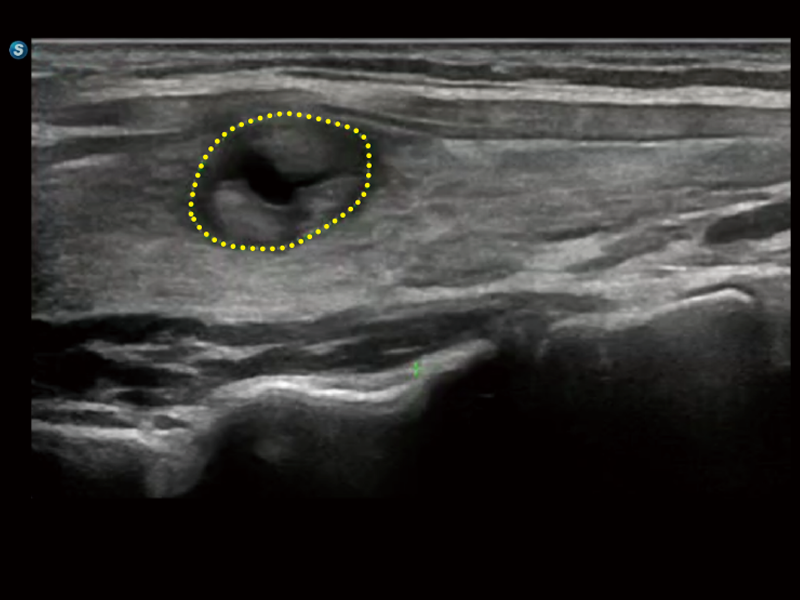

在传统血流的基础上优化扫查和算法策略,能够更好的抑制组织信息,提炼红细胞运动信息,得到更高帧频,高灵敏度和分辨率的血流信号,还原更真实的血流动力学。

通过光照模型,使二维血流显示出立体的效果,增加血流的敏感性、成束性,减少外溢。可以和其他不同的血流技术联合使用,融合不同技术的优势。轻松应对微小血管,增强血流的立体效果,提升视觉敏感性。

通过创新的Matrix E自适应滤波算法,能有效滤除软组织和噪声信号,最大限度保留超低速微细血流的信号;结合超长时间域算法,极大提升细微血流的敏感性和空间分辨率,更真实的反应组织、包块的血流灌注情况。